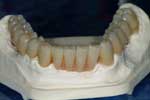

Caso 16

Riabilitazione superiore su impianti con protesi parzialmente rimovibili ed inferiore su impianti fissa

Sequenza fotografica (clicca sulle foto per ingrandire)